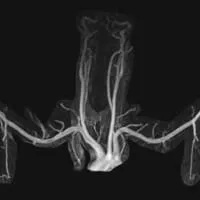

MR angiography is performed by injecting contrast into a peripheral vein, without an arterial catheter. MRA shows excellent arterial detail while eliminating most other structures, including bones. It requires no radiation. If used in conjunction with MRI, superb soft tissue detail is available. Excellent depiction of fibrous bands, muscle anomalies, bones, and the brachial plexus is possible with MRI.

This interactive media demonstrates magnetic resonance angiography (MRA) images in two different patients. One patient has a normal MRA. The other patient has compression of each subclavian artery. Note that the structures that cause this compression are not visible on MRA alone.